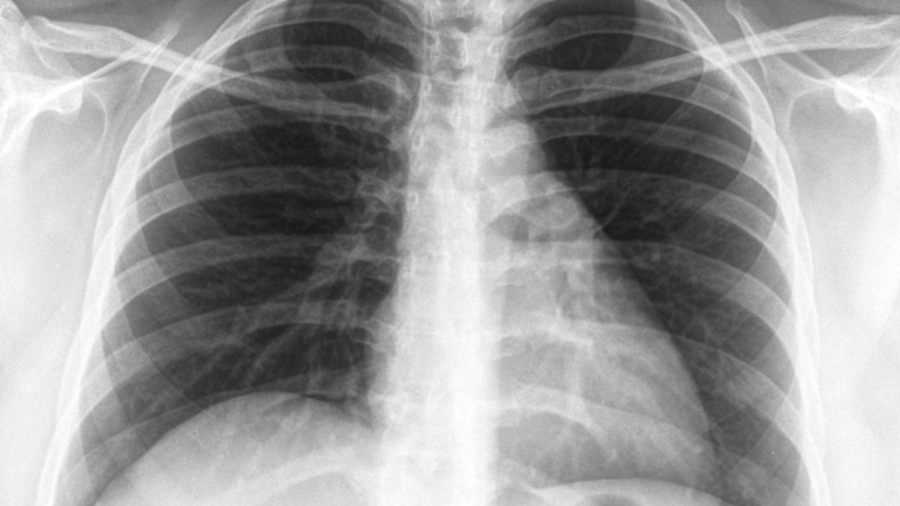

Започва Седмица на отворените врати за туберкулоза, съобщиха на сайта си от Столичната регионална здравна инспекция. Днес се отбелязва Световният ден за борба с туберкулозата.

Инициативата е в рамките на изпълнението на Националната програма за превенция и контрол на туберкулозата в България, а целта е да се повиши обществената информираност по отношение на заболяването.

В България диагностиката, лечението и профилактиката на туберкулозата са безплатни за всички, които се нуждаят, независимо от техния здравноосигурителен статус, посочват на сайта си от Националния център по заразни и паразитни болести. По инициатива на Световната здравна организация, всяка година на 24 март се отбелязва Световният ден за борба с туберкулозата.

Това е възможност за повишаване на осведомеността на населението за тежестта на болестта в национален и световен мащаб и за подобряване на усилията за грижа и превенция. Датата е избрана в чест на първото научно съобщение, направено от д-р Робърт Кох, който на 24 март 1882 г. обявява, че е открил причинителя на туберкулозата - бактерията Mycobacterium tuberculosis.